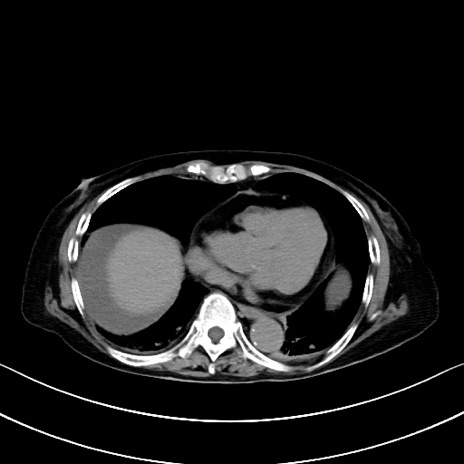

横断像